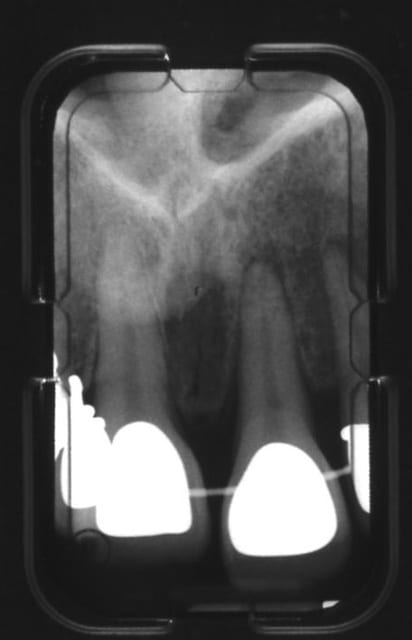

tu peux poster uniquement les rétros de 21 et 31, trop petit comme ceci

trop forte ;-)

31 ymhyhn - Eugenol

21 ekkiy1 - Eugenol

faudrait faire un test de vitalité, a voir d'autres avis..:)

je crains que le Mr du bouquin ait raison et que cela pende au bout de ta 21 aussi ds un avenir proche

tester effectivement la vitalité,surveillance radio et peut-être diminuer les forces en action(voir avec l'odf) pr une eventuelle reversibilité sur 21

des avis d'odf?

non sérieux les gars vous me faites peur là :-(

c'est pas parce que justement y a des forces de déplacement sur les dents et qu'il faut laisser le temps de se remanier au parodonte?...pitié....:-(

on est d'accord que vous les orthos, vous faites pas faire des bilans radios tous les 3 mois à vos patients pour voir comment vont leurs petites racines?...

Alors là, 3 mois après, alors qu'y a des forces sur mes dents, alors que ça se déplace, ben y a des images paro pas nettes, c'est sûr, mais c'est pas un peu normal??? Il faut pas laisser le parodonte se remanier?...(j'ai dit pitié....bouhouhou)